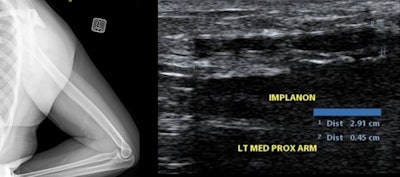

Left: Lateral radiograph of patient with a known dermal contraceptive implant. Right: Ultrasound image in the same patient.All figures courtesy of C. Paradise and S. Gaba and presented at EuroSafe 2025.